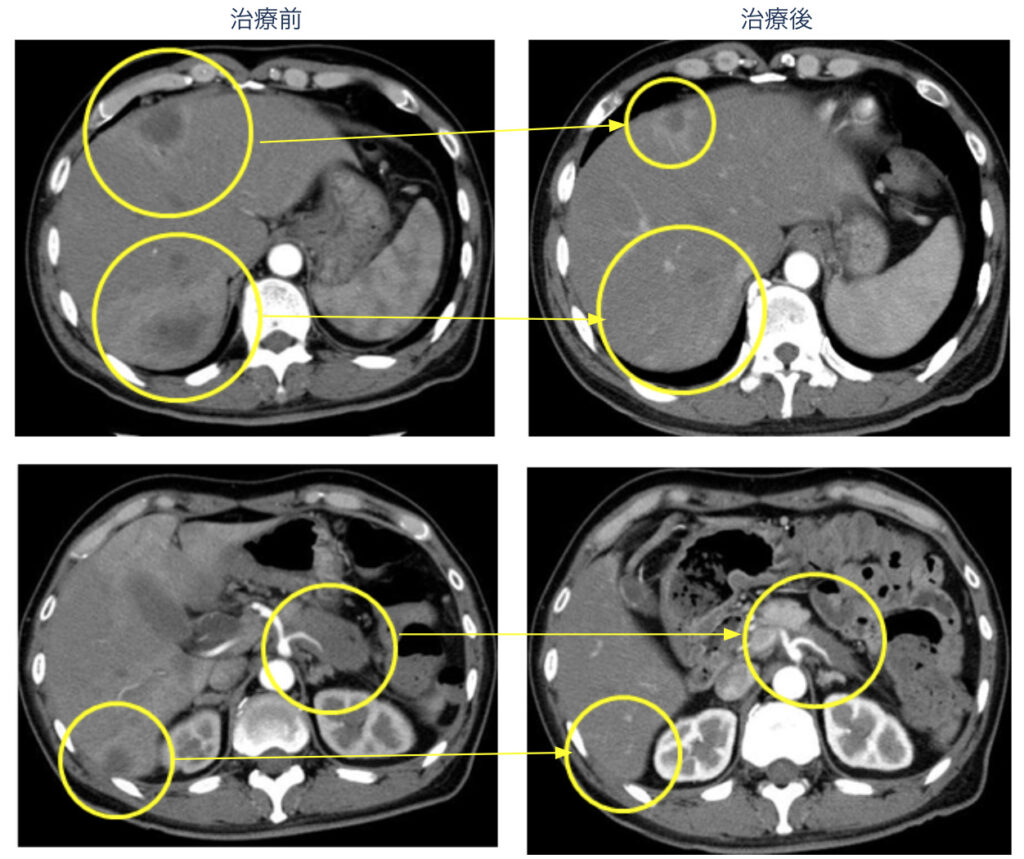

膵臓がんステージ4からの原発消失、肝転移消失、腫瘍マーカーの正常化